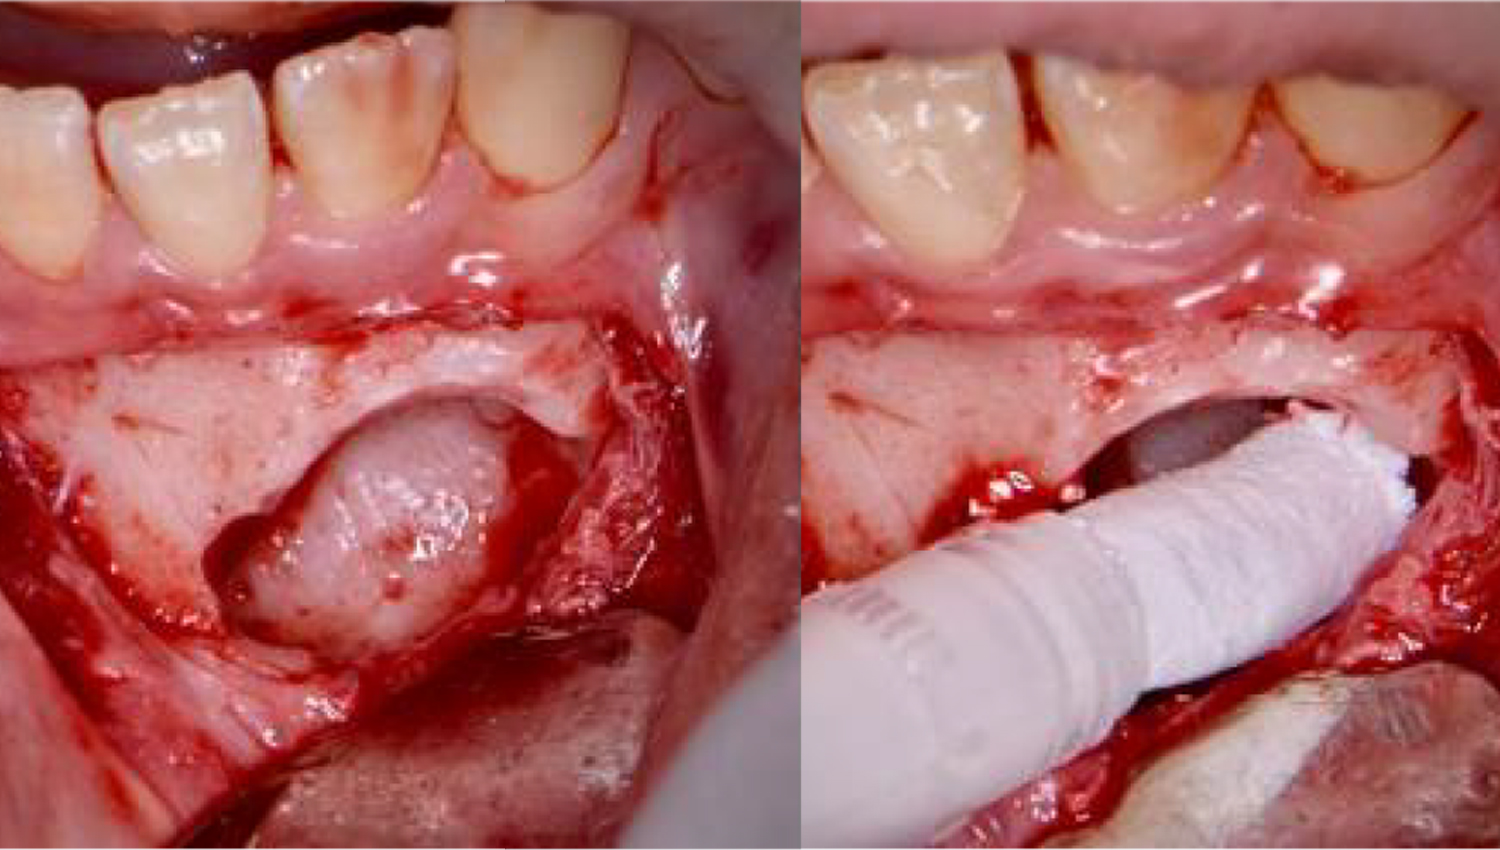

2.Surgical extraction of the impacted 43.

3.The bone defect was thoroughly debrided of all soft tssues and curretted with sharp Lucas hand currettes. Powerbone Dental Putty was used to graft the site, in order to assist and accelerate bone healing prior to initiating othodontic treatment.

4.4. The Bone defect filled with Powerbone Dental Putty. No barrier membranes were used (left picture). The sectioned impacted tooth after removal (right picture).

5.Two months post-op, clinical view showing excellent healing of the area. The patient is now ready to start the orthodontic treatment on the lower arch.